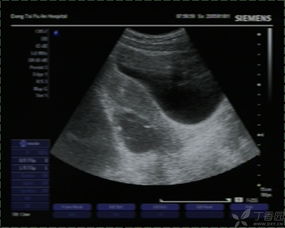

常規(guī)B超檢查是不需要空腹的,因?yàn)樗皇芟罋怏w的影響,常規(guī)B超檢查主要是通過(guò)B超的探測(cè)頭在腹部進(jìn)行探測(cè),從而檢查女性的子宮以及盆腔部位。并且懷孕的女性做B超,一般也是做常規(guī)B超檢查,而不是采取陰道B超檢查,因?yàn)槟軌蜃畲蟮谋Wo(hù)胎兒。

做常規(guī)B超檢查需要注意的一個(gè)地方,就是最好在B超檢查時(shí)能夠補(bǔ)充大量的水分,讓膀胱充盈起來(lái),這樣才能讓結(jié)果更加的準(zhǔn)確和清晰。早孕的女性需要補(bǔ)充水分,孕13周以后的女性在做常規(guī)B超檢查的時(shí)候就不需要喝水,讓膀胱充盈了。

肝膽胰等部位的B超檢查需要空腹,因?yàn)楦文懸任挥谂枨桓共康纳钐?,因此也就特別容易受到消化道氣體的影響,如果不空腹去進(jìn)行檢查就非常容易使結(jié)果產(chǎn)生偏差,從而達(dá)不到檢查的目的。

做B超檢查的時(shí)候是否空腹,主要是看具體是針對(duì)哪一部位的B超檢查,要具體情況具體分析。如果不知道自己做的B超檢查是否要空腹,需要提前就咨詢醫(yī)生,以免耽誤檢查的時(shí)間。